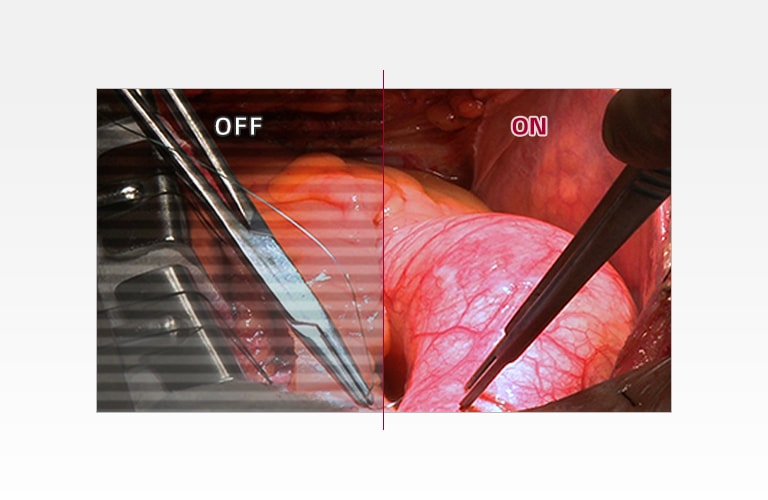

LG 手術用モニターのきめ細かな画質が、手術室の要件を満たします。LG 手術用モニターは、搭載の 27 インチのフル HD IPS ディスプレイで、作業効率を改善します。